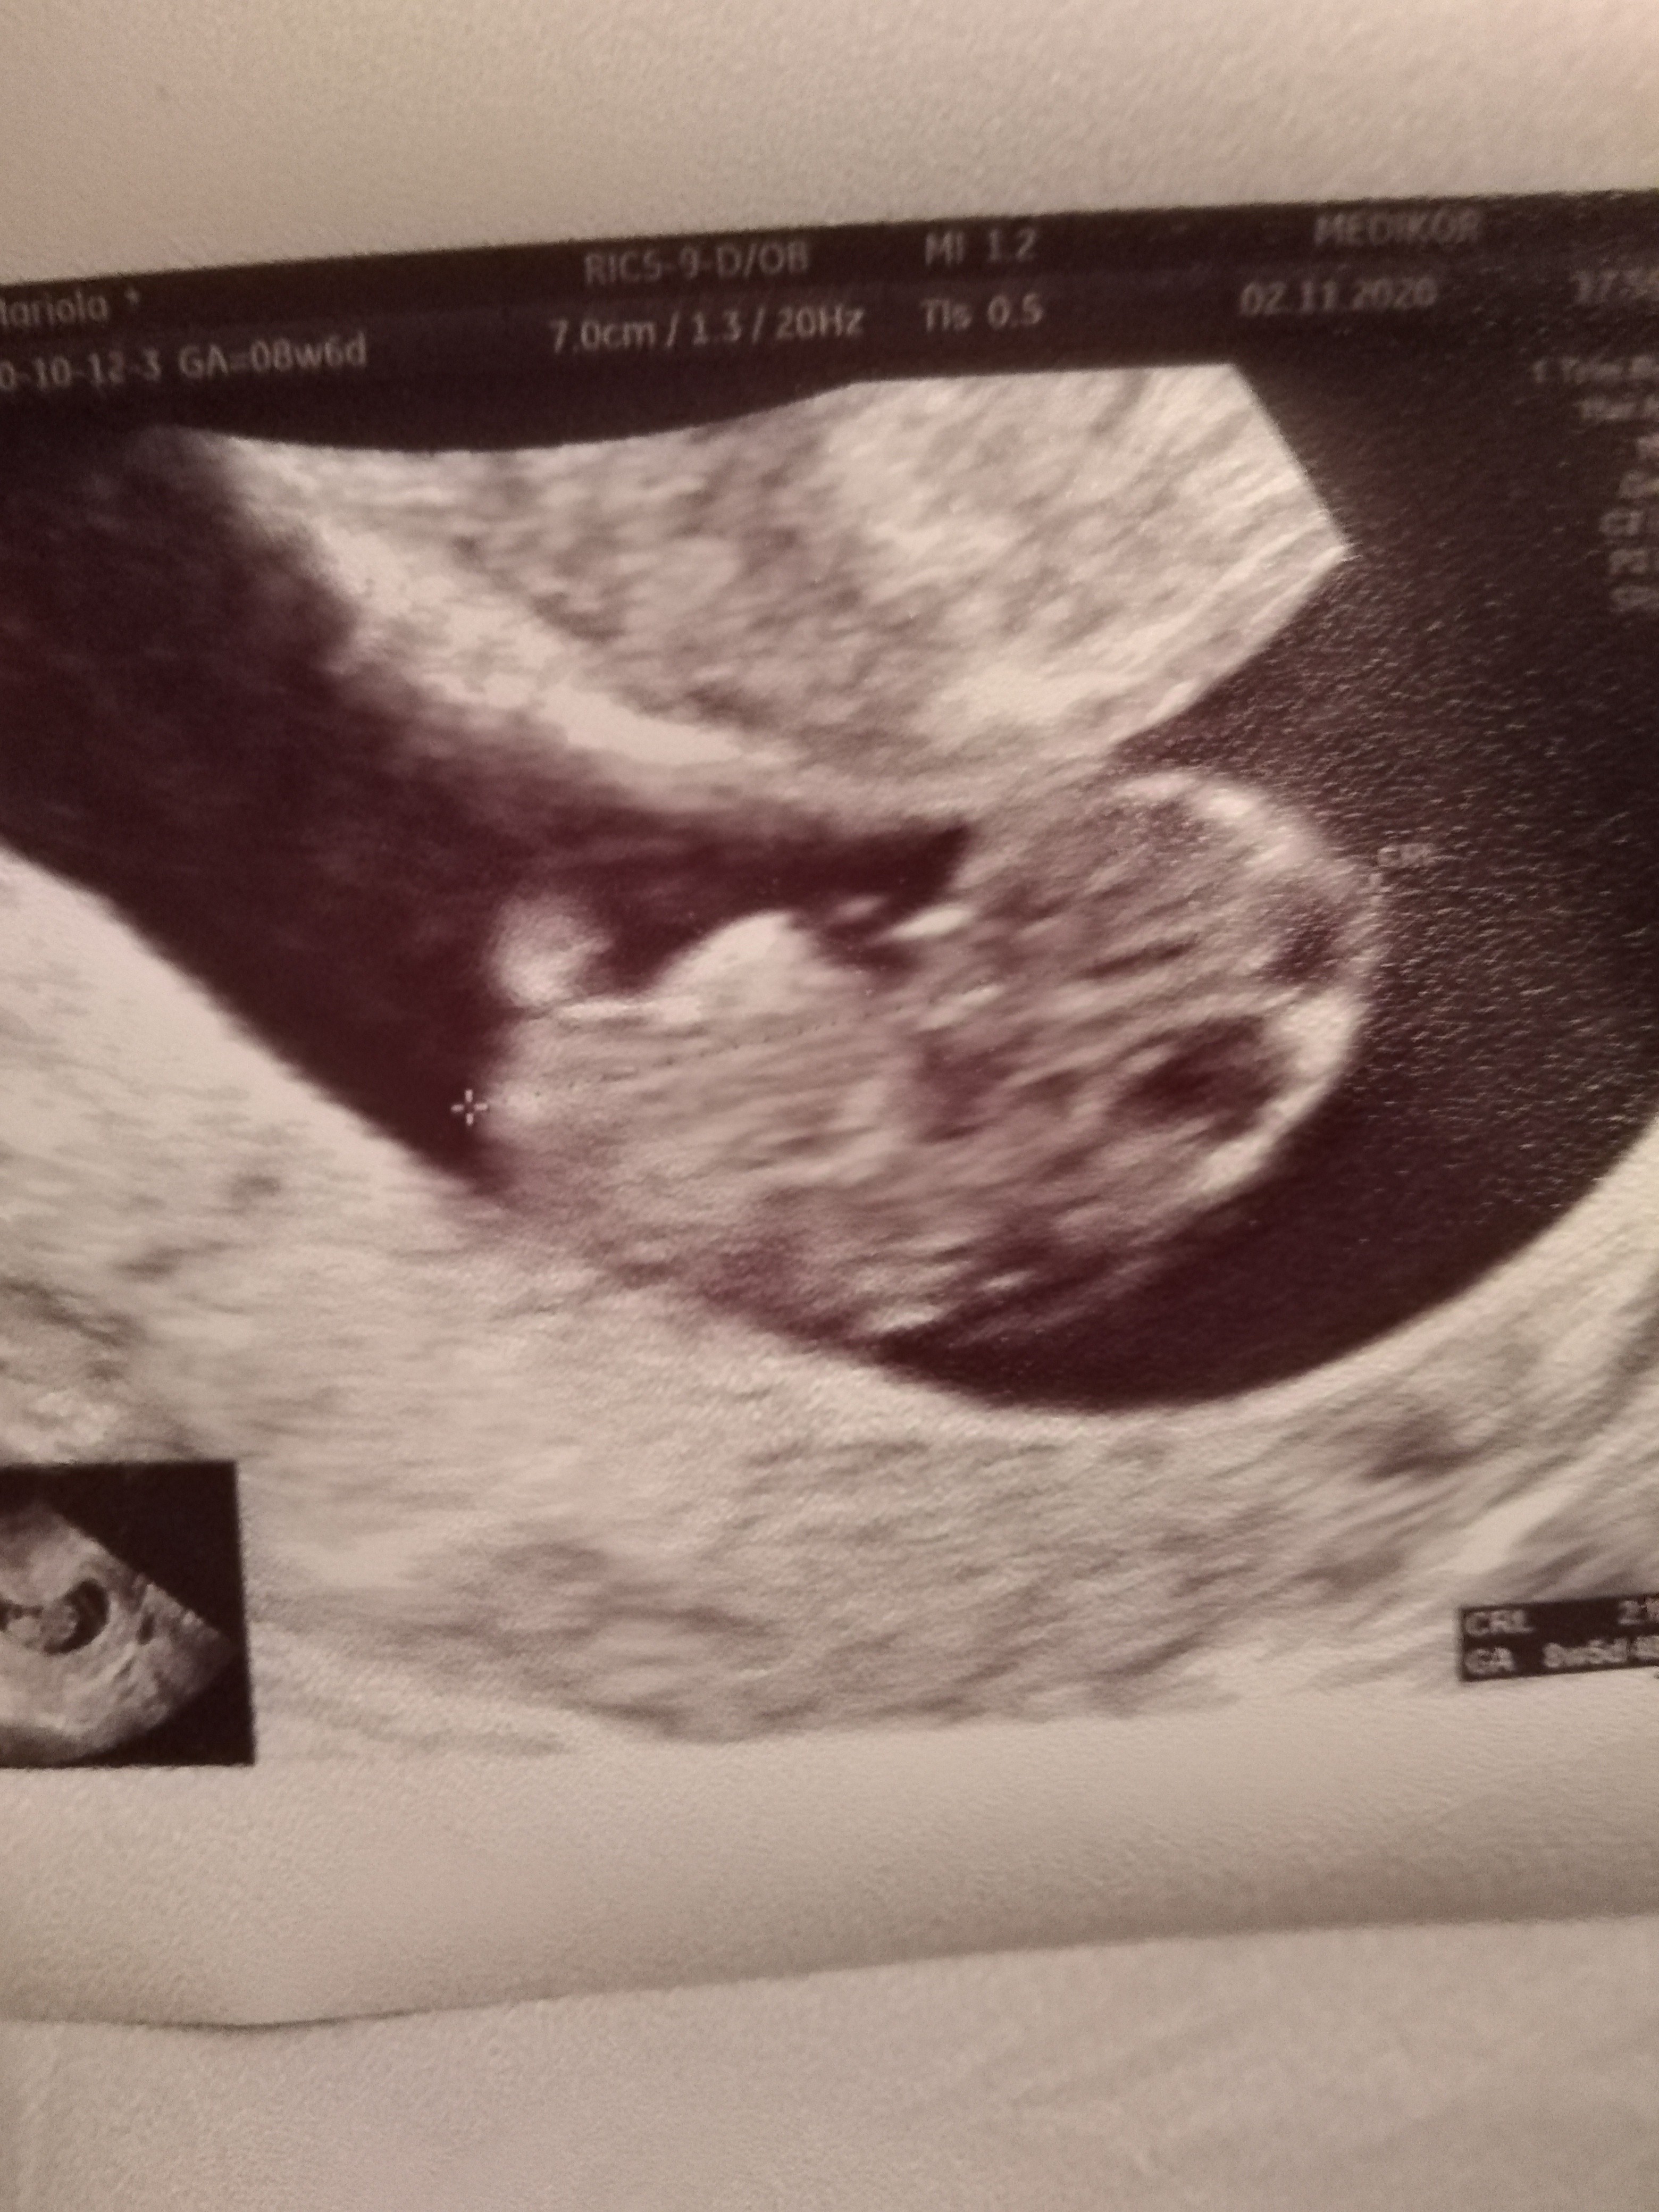

Jestem zakochana hihi :p

Załączniki

• IMG_20201102_180458.jpg

IMG_20201102_180458.jpg

1,8 MB · Wyświetleń: 122